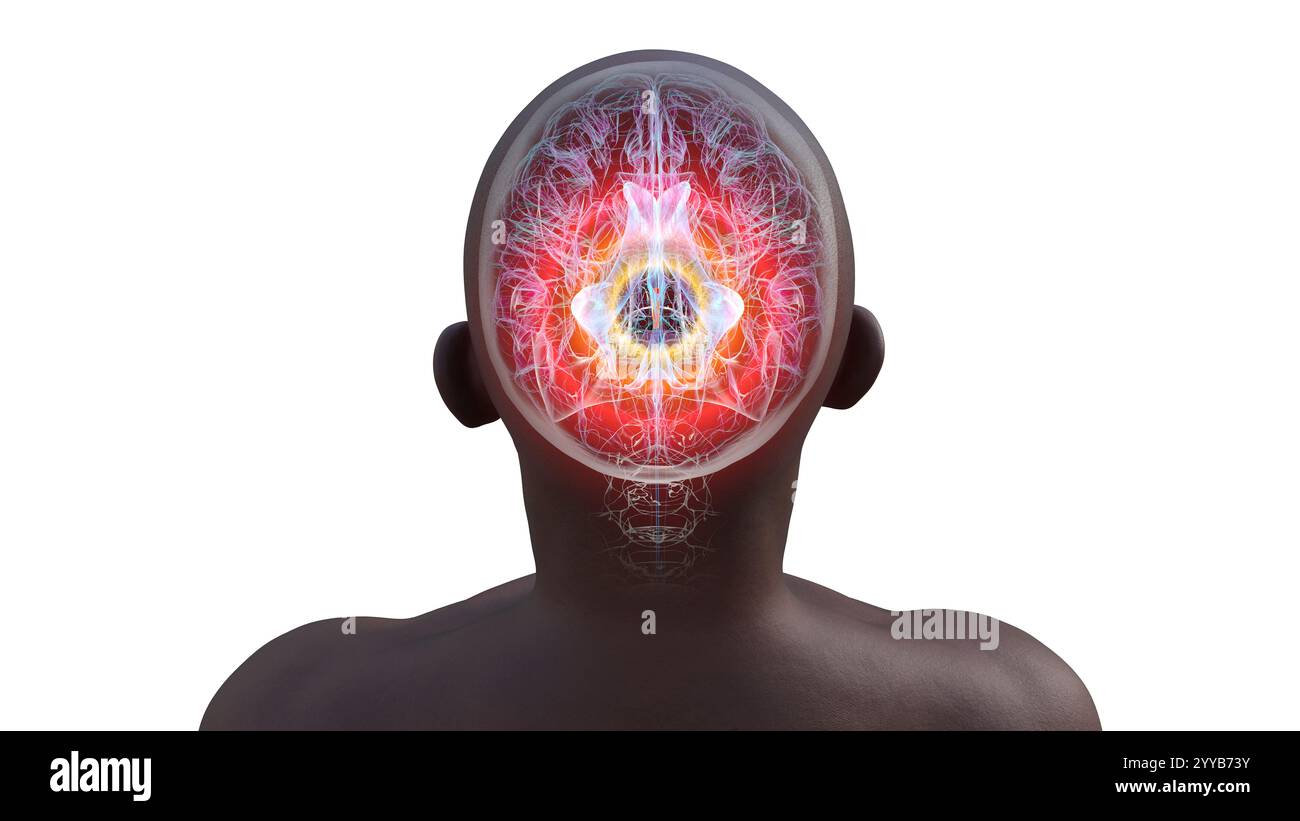

RF3C7H8A8–Abbildung des Gehirns mit hervorgehobenem Aquädukt (rot) und ventrikulärem System (blau), Darstellung des Liquorflusses.

RF3C7H8A6–Abbildung des Gehirns mit hervorgehobenem Aquädukt (rot) und ventrikulärem System (blau), Darstellung des Liquorflusses.

RF3C7H8AA–Abbildung des Gehirns mit hervorgehobenem Aquädukt (rot) und ventrikulärem System (blau), Darstellung des Liquorflusses.

RF3C7H8AF–Abbildung des Gehirns mit hervorgehobenem Aquädukt (rot) und ventrikulärem System (blau), Darstellung des Liquorflusses.

RF3C7H8A3–Abbildung des Gehirns mit hervorgehobenem Aquädukt (rot) und ventrikulärem System (blau), Darstellung des Liquorflusses.

RF2YX6R0H–Computerdarstellung des menschlichen Gehirns mit orangefarbenem Aquädukt und grünem Ventrikelsystem, die den Liquorfluss (CSF) zeigen. Rückansicht.

RF2YYB740–Computerdarstellung des menschlichen Gehirns mit orangefarbenem Aquädukt und grünem Ventrikelsystem mit Liquorfluss. Rückansicht.

RF2YYB755–Computerdarstellung des cerebralen Aquädukts (orange), eines schmalen Kanals im Mittelhirn, der den dritten und vierten Ventrikel verbindet und den Liquorfluss erleichtert. Rückansicht.

RF2YYB752–Computerdarstellung des cerebralen Aquädukts (orange), eines schmalen Kanals im Mittelhirn, der den dritten und vierten Ventrikel verbindet und den Liquorfluss erleichtert. Rückansicht.

RF2YYB75E–Computerdarstellung des cerebralen Aquädukts (orange), eines schmalen Kanals im Mittelhirn, der den dritten und vierten Ventrikel verbindet und den Liquorfluss erleichtert. Ansicht von unten.